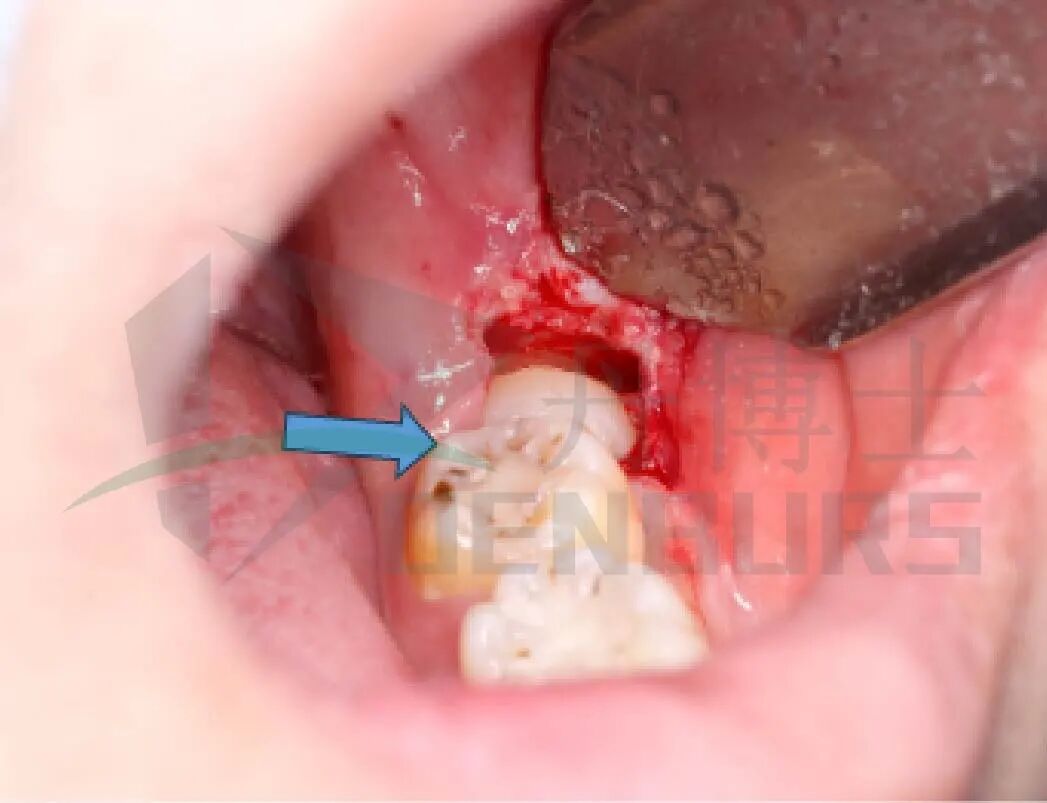

1)麻醉与翻瓣

局麻下切开并形成改良三角瓣,暴露患牙,解除软组织阻力。